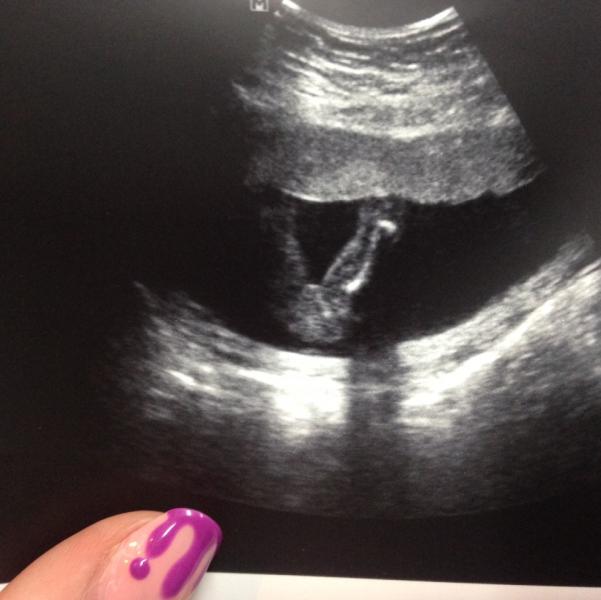

Вот наконец то и мы узнали что у нас будет раскошная великолепная кнопочка-девочка!🌺🌸😻гипер подвижная сказали(танцует)!мы так любим тебя,маленькая!!!расти здоровой❤️если что это наша жопка раскошная☺️

@marine9, это мы ходили на определение пола в СШУ к Макаровой(кстати шикарная врачиха), 1ый скрининг делала в Середавина!вот сегодня ровно 18 недель